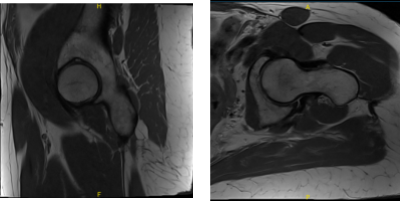

She presented MRI results for both of her hips that showed mild common hamstring tendinosis with a small intrasubstance tear and surrounding edema at the ischial tuberosity. Extensive avascular necrosis of the right femoral head. Degenerative changes in the lower lumbar spine for her left hip.

Extensive avascular necrosis involving the majority of the right femoral head and surrounding bone marrow edema extending into the femoral neck. Crescentic subchondral fracture line is seen medially without articular collapse or fragmentation.

There are mild osteophytic changes of the right femoral acetabular joint and a moderate joint effusion. Mild gluteus minimus tendinosis without a tear, for the right hip.

MRI Left hip non-contrast

MRI Right hip non-contrast